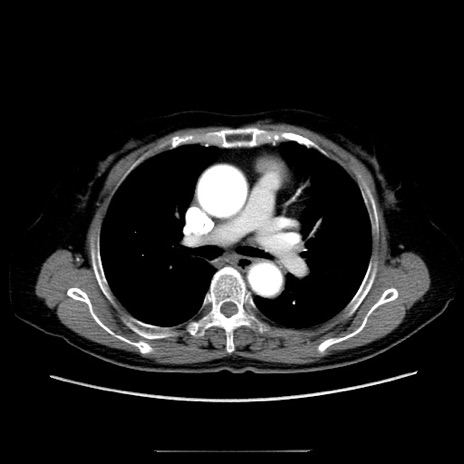

症例5(横断像)

【症例】70歳代女性

【主訴】お腹が張る

【現病歴】1週間くらい前から腹部膨満の自覚あり。昨日夜から増悪したため、本日救急外来受診。

【身体所見】意識清明、BT 36.5℃、BP 165/106mmHg、HR 80bpm、SpO2 98%、腹部:膨満、軟、自発痛・圧痛なし、触診にて不快感あり、腸蠕動音:減弱

【データ】WBC 12600、CRP 1.04